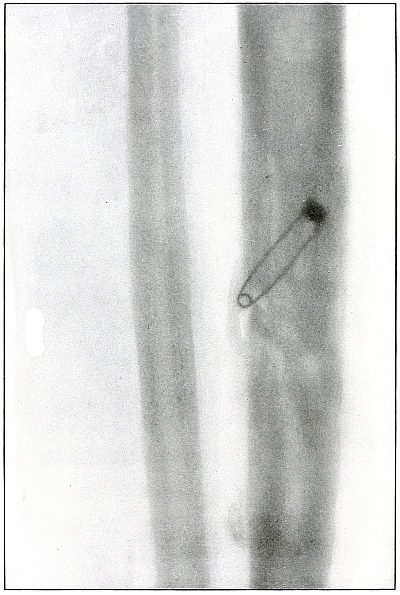

Plate 49.

[Pg 109]

Rifle—Plate 49.

LOWER EXTREMITY.

Gunshot Wound of the Right Thigh,

with Lodgment of the Bullet Behind the Femur.

There is no injury of the bone in this case, as the bullet lodged in

the muscles posterior to the lower third of the femur without striking

the bone. The lighter circular area of the larger end of the shadow

of the projectile shows that its base is farther from the plate than

its nose, which was probably flattened and bent by the ricochet which

reduced its velocity so as to give it but slight power of penetration.

It is not easy to determine from inspection of the plate which side of

the leg lay next to the plate.

With a history of the wound of the right thigh and with the outside

of the leg next to the plate, the projectile must have lain near the

plate on the outside behind the lower end of the femur, midway between

the skin and bone.

The markings seen on the bone are not concerned with the wound, as the

same effect in the plate is seen in the areas beside the bone.

The treatment is conservative; infection is rare.